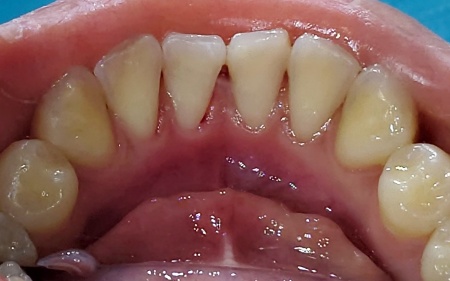

治療後

患者様には、保険診療内のクリーニングで歯石の除去が可能なことをお伝えし、同意いただきました。

歯科医院でのクリーニングでは、ご自身では落としにくい歯石や、歯ブラシが届きにくい歯間の汚れまで、専用の器具を使ってしっかりと取り除くことができます。

ただ、処置の際には一時的に出血や違和感が生じる場合がある点がデメリットです。

まず、超音波を利用した機械や専用器具を用いて、歯に付着しているプラークと歯石を除去する「スケーリング」を行います。

その後、プラークや歯石が再び付着しないよう、回転するブラシを用いて歯の表面をなめらかに磨き上げる「ポリッシング」を施して、治療を終了しました。

治療回数の目安 1回

おおよその費用 保険診療内